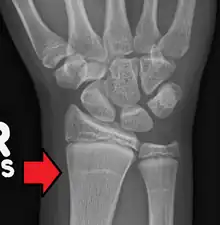

| Growth arrest lines in a child with an underlying bone disease | |

Growth arrest lines, also known as Harris lines, are lines of increased bone density that represent the position of the growth plate at the time of insult to the organism and formed on long bones due to growth arrest. They are only visible by radiograph or in cross-section. The age at which the lines were formed can be estimated from a radiograph. Harris lines are often discussed as a result of juvenile malnutrition, disease or trauma. Other studies suggest a reconsideration of Harris lines as more of a result of normal growth and growth spurts, rather than a pure outcome of nutritional or pathologic stress.[1] The lines are named after Henry Albert Harris (1886–1968), professor of anatomy at the University of Cambridge.[2]

Particularly, deficiencies in protein and vitamins, which lead to delayed longitudinal bone growth, can result in the formation of Harris lines.[3] During the process of endochondral bone growth, the cessation of osteoblastic activity results in the deposition of a thin layer of bone beneath the cartilage cap, potentially forming Harris lines.[4][5] Subsequent recovery, necessary for the restoration of osteoblastic activity, is also implicated in Harris line formation.[6] When matured cartilage cells reactivate, bone growth resumes, causing a thickening of the bony stratum. Therefore, complete recovery from periods of chronic illness or malnutrition also manifests as transverse lines on radiographs. Lines tend to be thicker with prolonged and severe malnutrition. Harris line formation typically peaks in long bones around 2-3 years after birth and becomes rare until adulthood after the age of 5. Additionally, Harris lines occur more frequently in boys than in girls.[7]